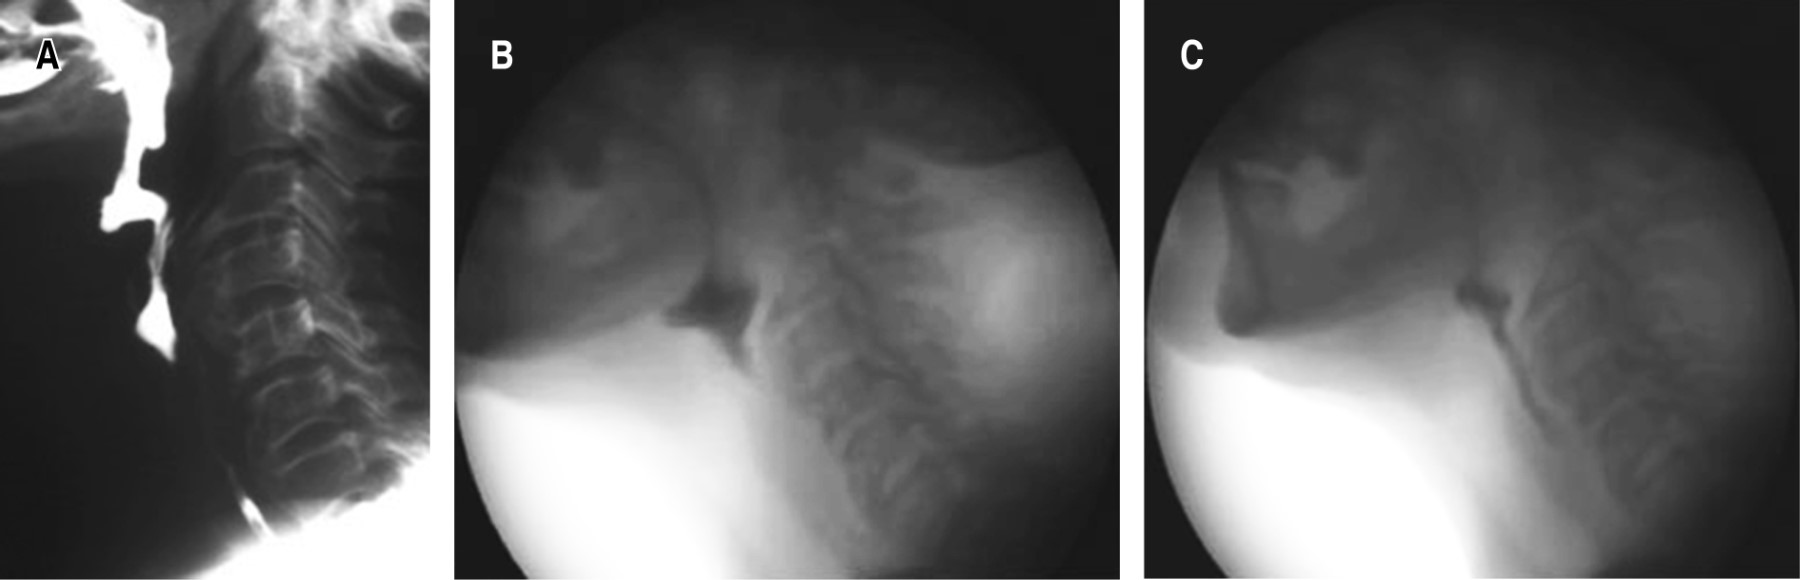

Para investigar la causa de la disfagia se realizaron radiografías de columna cervical, tomografía computada, videodeglución realizada por el Servicio de Fonoaudiología y una fibrolaringoscopia realizada por el Servicio de Otorrinolaringología. Estos estudios mostraron osteofitos en la cara anterior de la columna cervical a nivel de C3, C4 y C5 fusionados entre sí y a nivel de C6 y C7 (Figura 1).

Figura 1